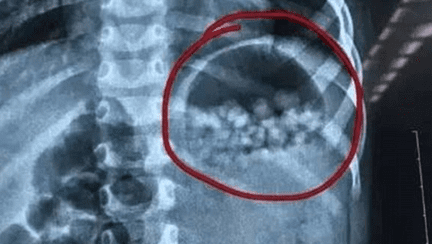

O fetita de 3 ani din China a ajuns de urgenta la spital in urma cu o saptamana, dupa ce parintii ei au aflat ca ceea ce ei cumparasera si ea mancase, crezand ca sunt bomboane, erau ceva deloc comestibil. Potrivit publicatiei The Sun, tatal fetitei nu avea habar cu ce isi hranise copilul, pana